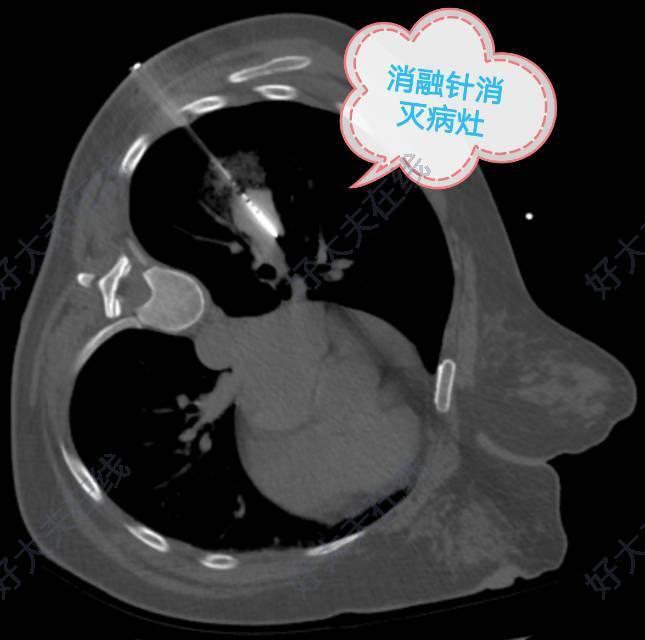

进行穿刺活检,微波消融

随后置入微波消融针进行微波消融对转移病灶进行毁损